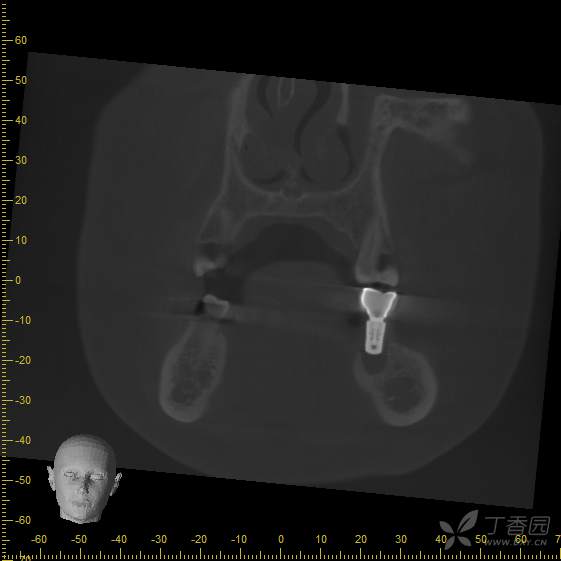

手术后3个月,可见种植体周围骨结合良好,行软组织成形(即二期),局麻下更换愈合帽。

戴牙后3个月,患者自述吃东西时疼痛,种植牙出现松动。

接诊时,36种植牙松1-2°,颊侧牙龈未见明显红肿。拍摄cbct后可见种植体周骨结合丧失,大量低密度影,骨吸收至根尖1/3,种植体浮出。